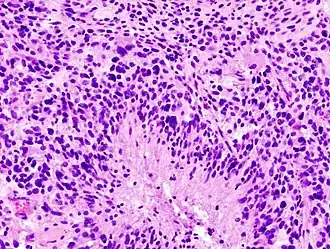

![]() Гистологический срез глиобластомы | |

Мультиформная глиобласто́ма (англ. Glioblastoma multiforme, GBM) — наиболее частая и наиболее агрессивная форма опухоли мозга, которая составляет до 52 % первичных опухолей мозга и до 20 % всех внутричерепных опухолей. Несмотря на то, что глиобластома является наиболее частой первичной опухолью мозга, на 100 000 жителей Европы и Северной Америки регистрируется всего 2—3 случая заболевания[1]. Термин «глиобластома» подразумевает два варианта этой болезни: гигантоклеточная глиобластома и глиосаркома.

Наиболее частые генетические нарушения при первичных глиобластомах — это: утрата гетерозиготности (LOH) 10q (69 %), затем амплификация EGFR (34 %), мутация TP53 (31 %), гомозиготная делеция p16INK4a (31 %) и мутации PTEN (24 %). Во вторичных глиобластомах часты мутации TP53 и LOH 10q (65 % и 63 %), в то время как другие генетические нарушения редки[38].